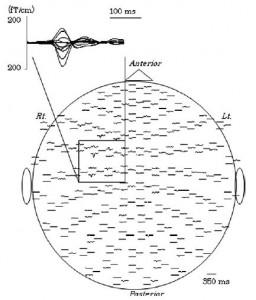

Onishi H, Sugawara K, Yamashiro K, Sato D, Suzuki M, Kirimoto H, Tamaki H, Murakami H, Kameyama S. Effect of the number of pins and inter-pin distance on somatosensory evoked magnetic fields following mechanical tactile stimulation. Brain Research, 2013, 1535:78-88

Onishi H, Sugawara K, Yamashiro K, Sato D, Suzuki M, Kirimoto H, Tamaki H, Murakami H, Kameyama S. (2013) Neuromagnetic activation following active and passive finger movements. Brain and Behavior 3:178–192.

Onishi H, Oyama M, Soma T, Sugawara K, Kirimoto H, Murakami H, Kameyama S.(2011) Muscle-afferent projection to the sensorimotor cortex after voluntary movement and motor-point stimulation: An MEG study. Clinical Neurophysiology. 122: 605-610